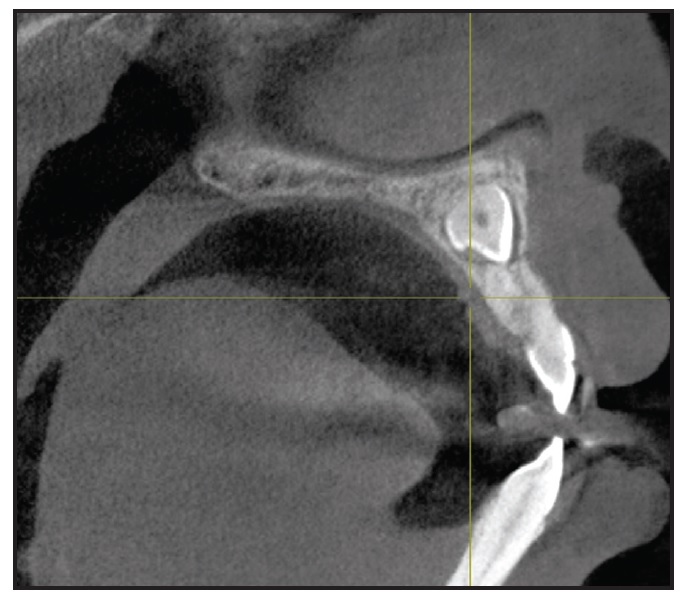

The panoramic radiograph revealed impacted upper permanent canines, a horizontally impacted lower right third molar, and an unrestorable lower right first permanent molar. Sagittal cone-beam computed tomography (CBCT) of the upper arch located the impacted canines near the upper midline, past the apex of the upper central incisors (Fig. 2).

Fig. 2 Impacted upper canines visible on sagittal cone-beam computed tomography.